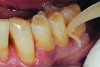

Fig 2 and Fig 3. In Case 1, occlusal (Fig 2) and buccal (Fig 3) preoperative views of defective Class I and Class V amalgam restorations on mandibular first permanent molar.